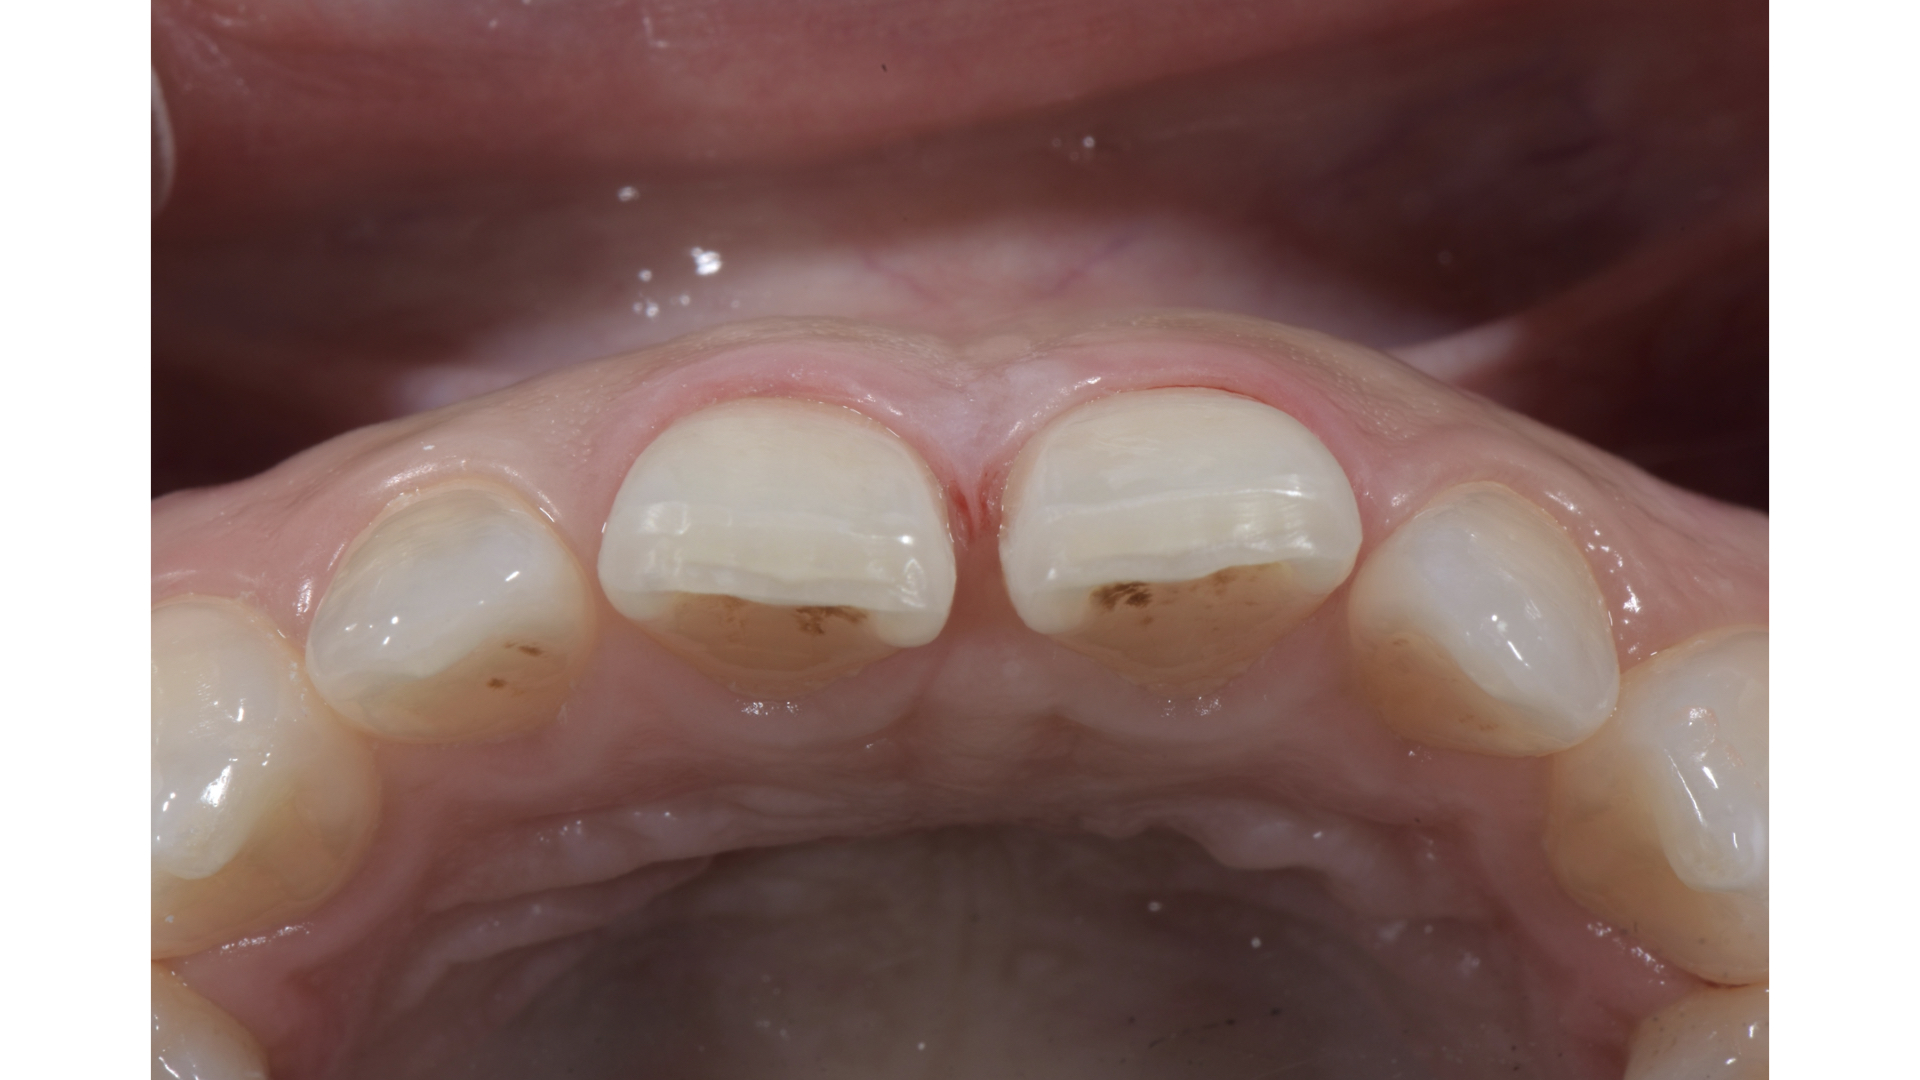

微創修磨